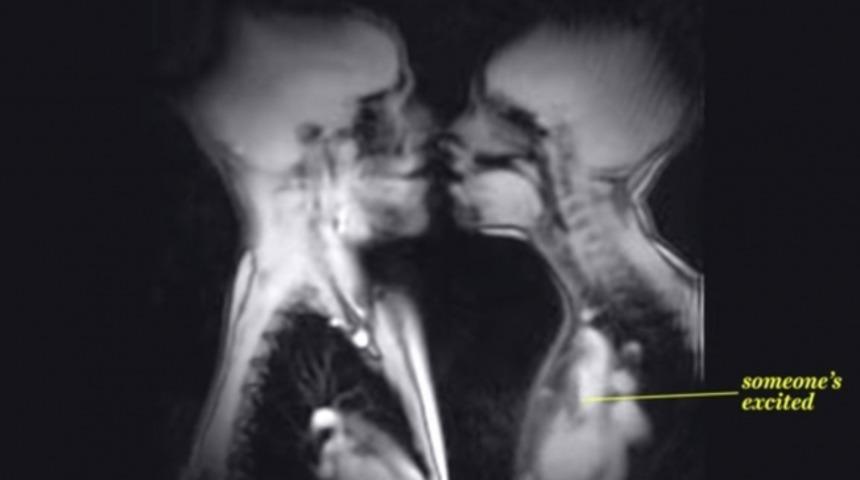

Bu son derece ilginç videoda, Manyetik Rezonans Görüntüleme (MRI) cihazı kullanılarak çekilmiş birçok görüntü göreceğiz. Görüntüler arasında gösterilen birçok şey, zaten daha önceden muhtemelen görmüş olabileceğiniz şeyler: yutkunmanın nasıl gözüktüğü, bir bebeğin ana rahminde nasıl gözüktüğü, vs. Bunların büyük bir kısmı zaten uzun süredir bilinen ve çekilen görüntülerden oluşuyor... Biri hariç: seks.

Videoda, MRI makinası içerisinde bilimsel bir araştırma için seks yapan 2 kişinin sinematik görüntüleri yer alıyor. Normalde bu tür bir çekimin X-Işını veya CT taraması ile yapılması mümkün değil, çünkü yoğun radyasyon sağlığı tehdit ediyor. Ancak MRI'da zararlı radyoaktif ışınlar kullanılmadığı için böyle bir tehlike yok. Çok sayıda fotoğraf herhangi bir tehlike oluşmaksızın çekilebiliyor ve bir araya getirilerek videoya dönüştürülebiliyor.